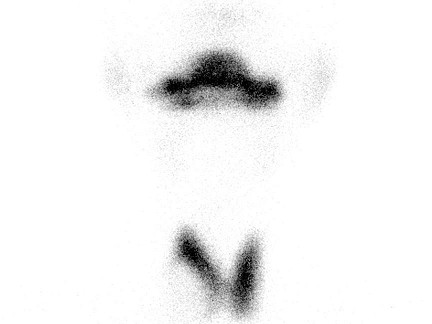

[多选题] 女,43岁,发现颈部包块1月,体检:颈部包块质硬,无压痛。TcO甲状腺显像如图,对右叶甲状腺结节的描述正确的是()A .是“热结节”B .是“冷结节”C .是“温结节”D .可能为甲状腺癌E .可能为甲状腺瘤伴出血

[多选题] 女,43岁,发现颈部包块1月,体检:颈部包块质硬,无压痛。99TcmO4-甲状腺显像如图,对右叶甲状腺结节的描述正确的是()。A . 是“热结节”B . 是“冷结节”C . 是“温结节”D . 可能为甲状腺癌E . 可能为甲状腺瘤伴出血